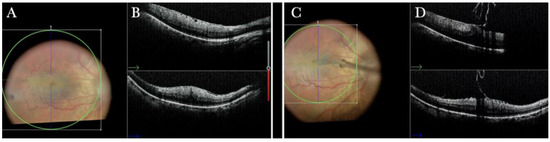

Figure 11.

(A) Microscope view of the macular area in case of myopic traction maculopathy in stage 4C (macular detachment with full-thickness macular hole (FTMH)) after implanting a macular buckle. The transillumination of a fiber optic inserted into the buckle allows us to guess the location of the buckle itself. The inner limiting membrane (ILM) flap is visibly stained blue. The FTMH is not visible. (The white box indicates the field-of-view of the OCT scan, the green line within the green box shows the scan plane) (B) The Intraoperative Optical coherence tomography (i-OCT) B horizontal (green arrow) and vertical scan shows very clearly the indentation of the macula from the scleral side due to the presence of a macular buckle. The white arrowhead shows the FTMH, which is not over the buckle. (C) Same view as in A after repositioning the macular buckle. (The white box indicates the field-of-view of the OCT scan, the green line within the green box shows the scan plane) (D) i-OCT B horizontal (green arrow) and vertical scan showing very clearly the indentation of the macula from the scleral side due to the presence of a macular buckle. The white arrow shows the FTMH, which is now well-positioned over the buckle.